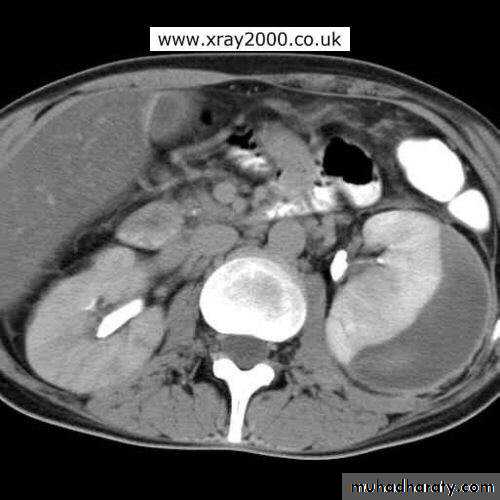

CT scan: right renal abscess

CT scan: Left renal abscess